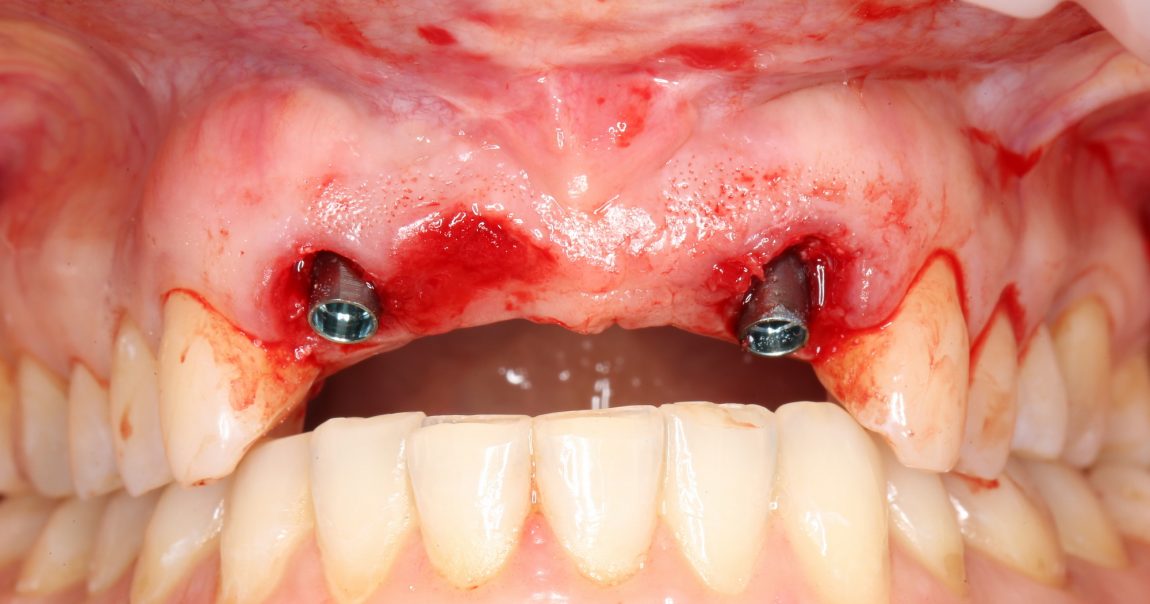

Таким образом, мы устанавливаем оба имплантата:

Наш физиодиспенсер позволяет измерять крутящий момент при установке — у нас получилось среднее значение около 20 Нсм. Этого достаточно для немедленного протезирования.

Но прежде, чем мы к нему перейдём, еще раз проверим положение имплантатов:

Поскольку мы планируем в качестве временных использовать абатменты Esthetic Cap, необходимо правильно ориентировать имплантаты по граням внутреннего шестигранника. Это несложно сделать по имплантоводу (на нём есть насечки) или предустановленному абатменту TempBase.

Фиксируем Esthetic Cap на имплантаты. Усилие при установке — 14 Нсм (больше ключ Xive не позволяет):

Еще раз проверим позиционирование имплантатов:

Поскольку трансгингивальная часть временного абатмента Esthetic Cap полностью перекрывает апертуру лунки зуба, мы можем обойтись без швов. Вообще без швов.